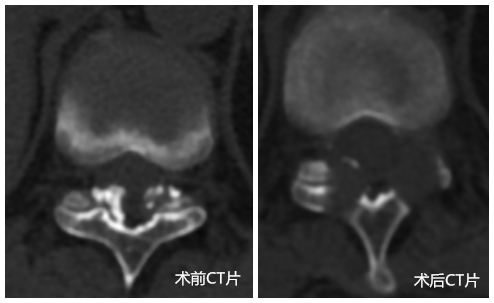

• 宫颈癌肿拳头大,射波刀治疗90天全消——一宫颈癌患者受病困扰两年最终获治

宫颈癌肿拳头大,射波刀治疗90天全消——一宫颈癌患者受...

广西中医药大学附属瑞康医院肿瘤科运用射波刀+中药治疗肿瘤可达到不开刀、无出血、不麻醉、无疼痛的良好效果。近期,一名宫颈癌Ⅲ期B合并大出血...